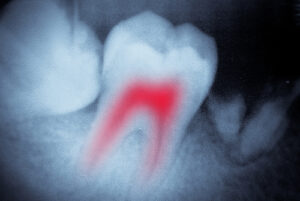

“Will it hurt?” “How long will it take?” “What should I expect when getting a…